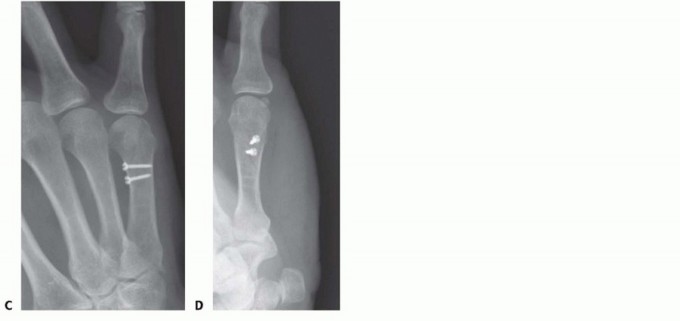

TECH FIG 4 • A-C. Patient with torsional injury to long and ring fingers leading to spiral fractures of the third and fourth metacarpals. The combined injury made it possible for malrotation to develop. D.

TECH FIG 4 • (continued) G,H. Motion at 6 weeks after surgery. The periosteum is elevated at the fracture site to assist with assessment of fracture reduction. As much of the interosseous muscle is left attached to the metacarpal as feasible to preserve blood supply to the bone.The fracture is reduced and provisionally stabilized with reduction clamps (TECH FIG 4D).

LAG SCREW FIXATION

Long oblique and spiral fractures whose lengths are at least twice the diameter of the bone at the level of the fracture are amenable to limited fixation with screws only (see TECH FIG 4A-C).Appropriately sized lag screws (1.4 to 2.7 mm) are placed. Typically, two or three screws are used (TECH FIG 4E,F).The first screw is placed perpendicular to the fracture in order to compress it and the second screw is placed perpendicular to the bone to resist longitudinal forces.In order to get proper compression with a lag screw construct, it is important to overdrill the near cortex.When using a 2.0-mm screw system, a 1.5-mm drill bit is used to drill both cortices. The near cortex is then overdrilled with a 2-mm drill bit.A countersink is used to maximize contact between the head of the screw and the bone. The size of the screw is measured and an appropriately sized screw is placed.The periosteum and interosseous muscle fascia are reapproximated to cover the screws. The juncturae tendinum are repaired and the skin is closed in standard fashion.The hand is then immobilized with the MP joints flexed 70 to 90 degrees with a forearm-based splint. Early motion can be started as early as 4 to 7 days, depending on fracture stability (TECH FIG 4G,H).